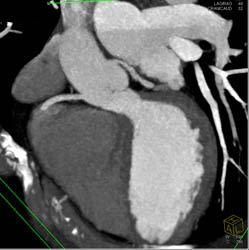

Diagnosis

LAD Disease